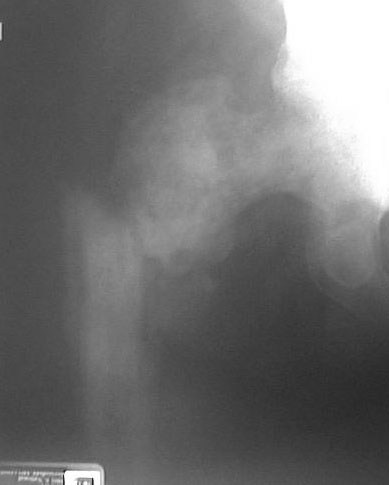

Subject: Subtrochanteric pathologic fracture

AP Hip

This patient is a 61 year old with prostate ca metastatic to bone. Noapparent metastases to the liver, lungs or brain. Serum calcium isnormal. No apparent impending fractures elsewhere. He is on hormonetreatment for his prostate ca. He was ambulatory prior to falling inthe shower and fracturing his hip.

I've considered a Synthes IM rod with their proximal spiral locking blade forthe femoral neck with cement augmentation. One of my concerns with is reamingthe medullary canal without penetrating his very fragile appearing cortex thatmay be no firmer than the metastatic tissue in the medullary canal.

The other consideration that comes to mind is a calcar replacing hemiprosthesis. However, the bone of the calcar may be very weak ornonexistent. Getting a secure attachment of the trochanter may bedifficult due to the soft bone from severe involvement of the bone ofthe trochanter and I would be concerned that it might not heal.

From: barrick

It looks like the entire head and neck of the femur are involved with tumor.So I would do some type of hemiarthroplasty replacement of the entireproximal portion of the femur---provided there is no involvement of thepelvic side of the hip joint.

The images on my screen are not adequate to assess the tumor's proximalextent. A CT scan may allay your fears of proximal fixation. I have foundthat the full length IM hip screw (34-42cm) works well for this pathologicprocess, and can be placed with a minimal surgical insult. The 18mm proximalnail expansion replaces the tumorous intramedullary contents and is anexcellent buttress, and the sliding screw seems to offer better & dynamicpurchase of the proximal fragment than interlocking screws, provided it isplaced dead center and very deeply.